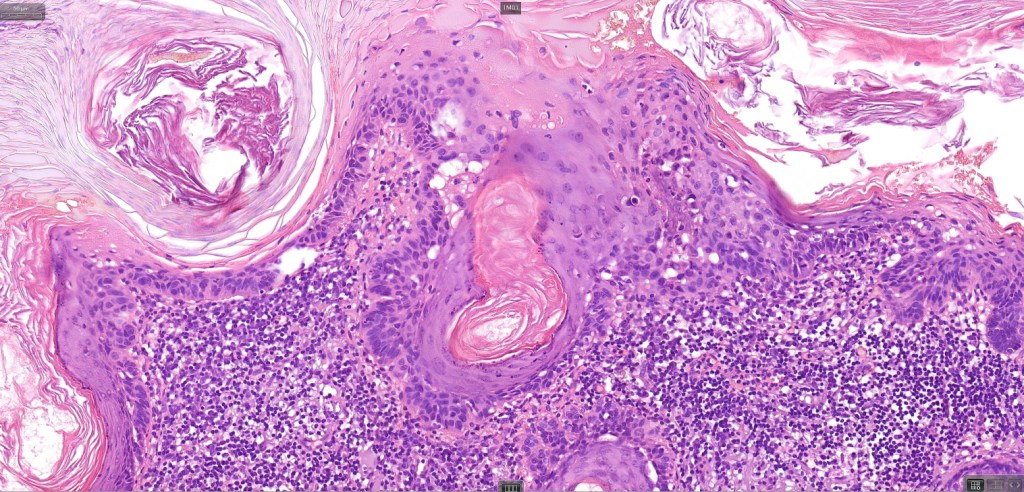

•Hyperkeratotic/hyperplastic actinic keratosis represents the prototype-alternating hyperkeratosis & parakeratosis- the former overlies the follicular & sweat duct ostia (Freudenthal funnel) while the latter overlies the interadnexal dysplastic epithelium & ranges from basal cell layer though to full thickness dysplasia (Bowenoid actinic keratosis); budding from the epidermis is a common finding; dysplastic epithelium commonly forms a mantle around the follicles and superficial sweat ducts

•Variable lack of maturation, nuclear irregularity, pleomorphism & mitotic activity

•Solar elastosis

.Superficial dermal lymphohistiocytic infiltrate